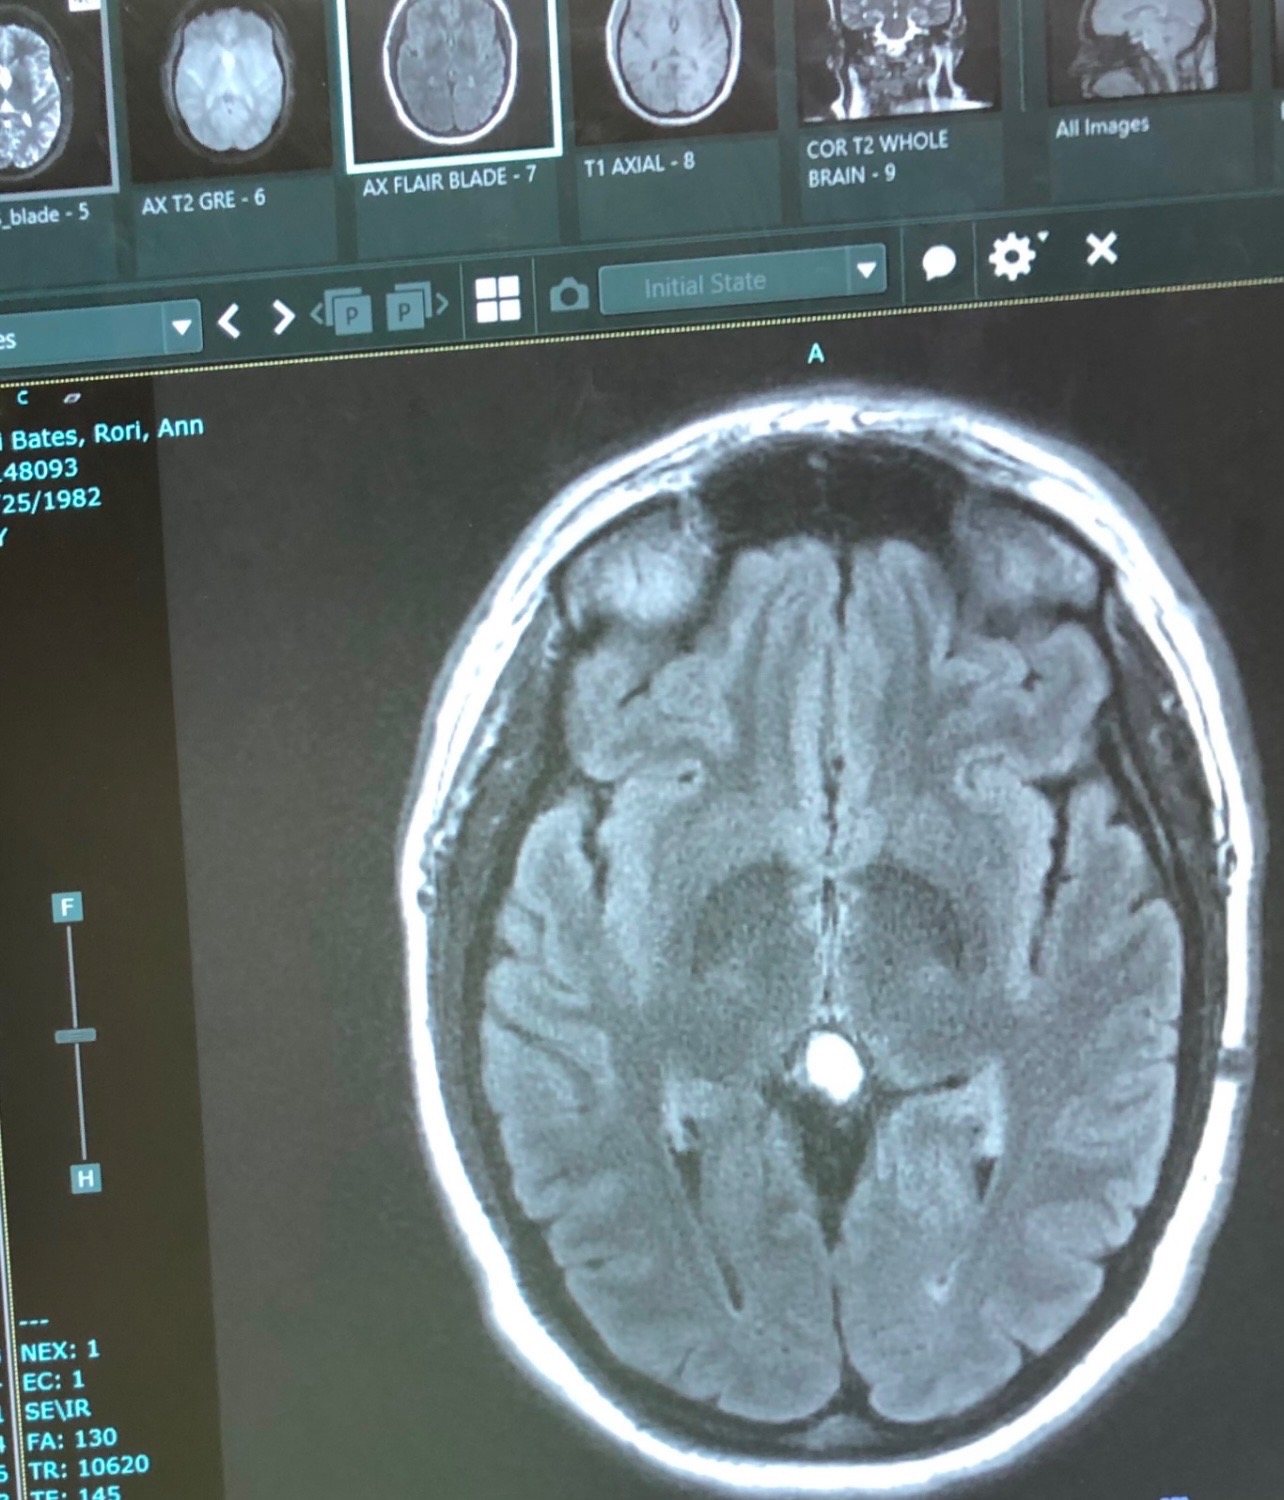

Over the last 10 + years Rori has developed Myoclonic and Tonic clonic seizures. They have rapidly increased and affect all of her daily life. Her last 43 hour brain scan (EEG) showed over 150 seizures. Over the last 2 years the seizures and the medication side effects got so bad she had to stop her business. Some days she has problems forming basic sentences, cooking, and even basic chores. Nathan is trying as hard as he can to continue to support their family while driving Rori to all the doctors appointments from eastern Washington to UW medical in western Washington for doctors, all shopping pretty much everything that needs to be done. This coming week, Rori will be going in for a surgery that is like a pace maker for her brain that will send a pulse through her brain to help send shock waves to hopefully help her have less seizures. Between this and the 4 medications she takes, she hopes to regain somewhat of a normal life for a bit. After surgery, every 1.5 to 2 weeks Nathan will need to take the day off, take Rori to the doctor to have the device calibrated for the next 6 plus months. Between this and missing work, and the 200 miles round trip it’s going to add up. The surgery bill, the hospital stay, the hotel stay for Nathan, and much more is all beginning to add up and weighing on Nathan’s shoulders as he tries to care for his wife.